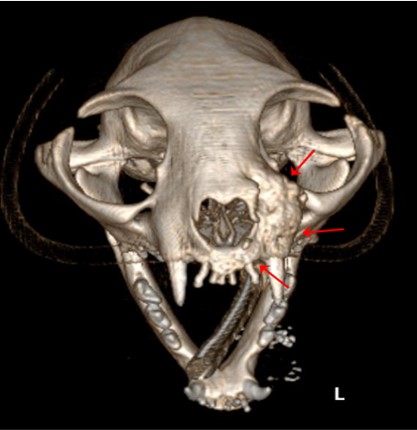

CT는 신체의 여러 각도에서 x-선을 투과시킨 후 단면 영상과 3차원적 입체영상을 얻을 수 있어 해부학적 구조와 병적 변화 정도를 정확하고 빠르게 평가할 수 있습니다.

CT 검사는 각종 종양과 염증, 외상 및 신체 기형과 같은 질환의 진단에 유용하게 사용될 수 있으며 수술이 지시되는 경우에도 진단을 넘어 정확한 해부학적 구조의 평가가 가능해져 이를 통해 수술 계획을 수립할 수 있습니다.

건국대학교 동물암센터에서 보유하고 있는 CT는 여러 개의 디텍터를 갖고 있는 multi-detector CT (MDCT)로써 촬영 시간 및 피폭량을 최소화 할 수 있는 장점이 있습니다. 여러 개의 디텍터를 통해 선명한 영상을 빠르게 구현해 냄으로써 진단의 정확성을 높일 수 있습니다.

- 종양 진단 (두경부, 흉강, 복강, 사지 골격) 및 전이 평가

두경부 종양 -